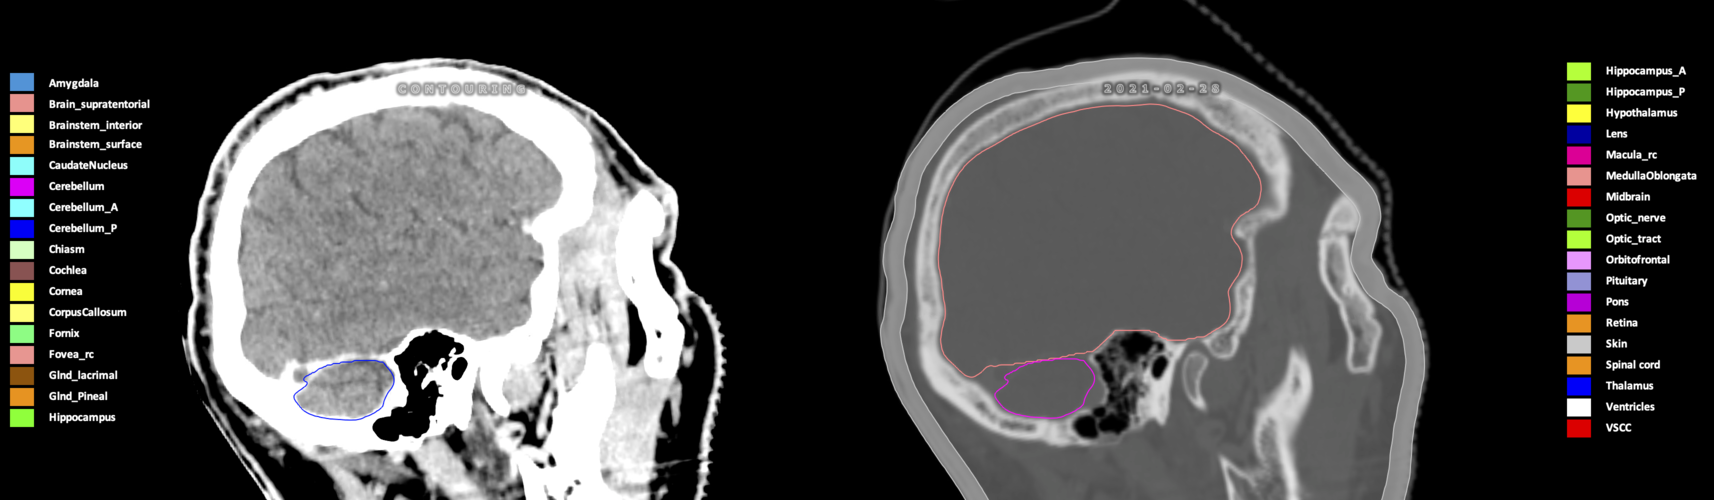

Three-dimensional delineation of the 25 consensus OARs for neuro-oncology are shown on CT (WW/WL 120/40, 3000/600), 3T MR images, (T1Gd, T2FLAIR 1mm) and 7T MR (MP2RAGE 0.7 mm). All are presented in transversal, sagittal and coronal view.

Included are all OARs known to be relevant for radiation-induced toxicity in neuro-oncology: brain, brainstem (midbrain, pons, medulla oblongata), chiasm, cerebellum (anterior & posterior), cochlea, cornea, hippocampus (anterior & posterior), hypothalamus, lens, lacrimal gland, optic nerve, pituitary, skin, and vestibular & semicircular canals. To further facilitate research on cognition, vision and radiological changes after irradiation of the brain, potential clinically-relevant OARs are included: amygdala, caudate nucleus, cerebellum (anterior & posterior), corpus callosum, fornix, macula, optic tract, orbitofrontal cortex, periventricular space (PVS), pineal gland, and thalamus.